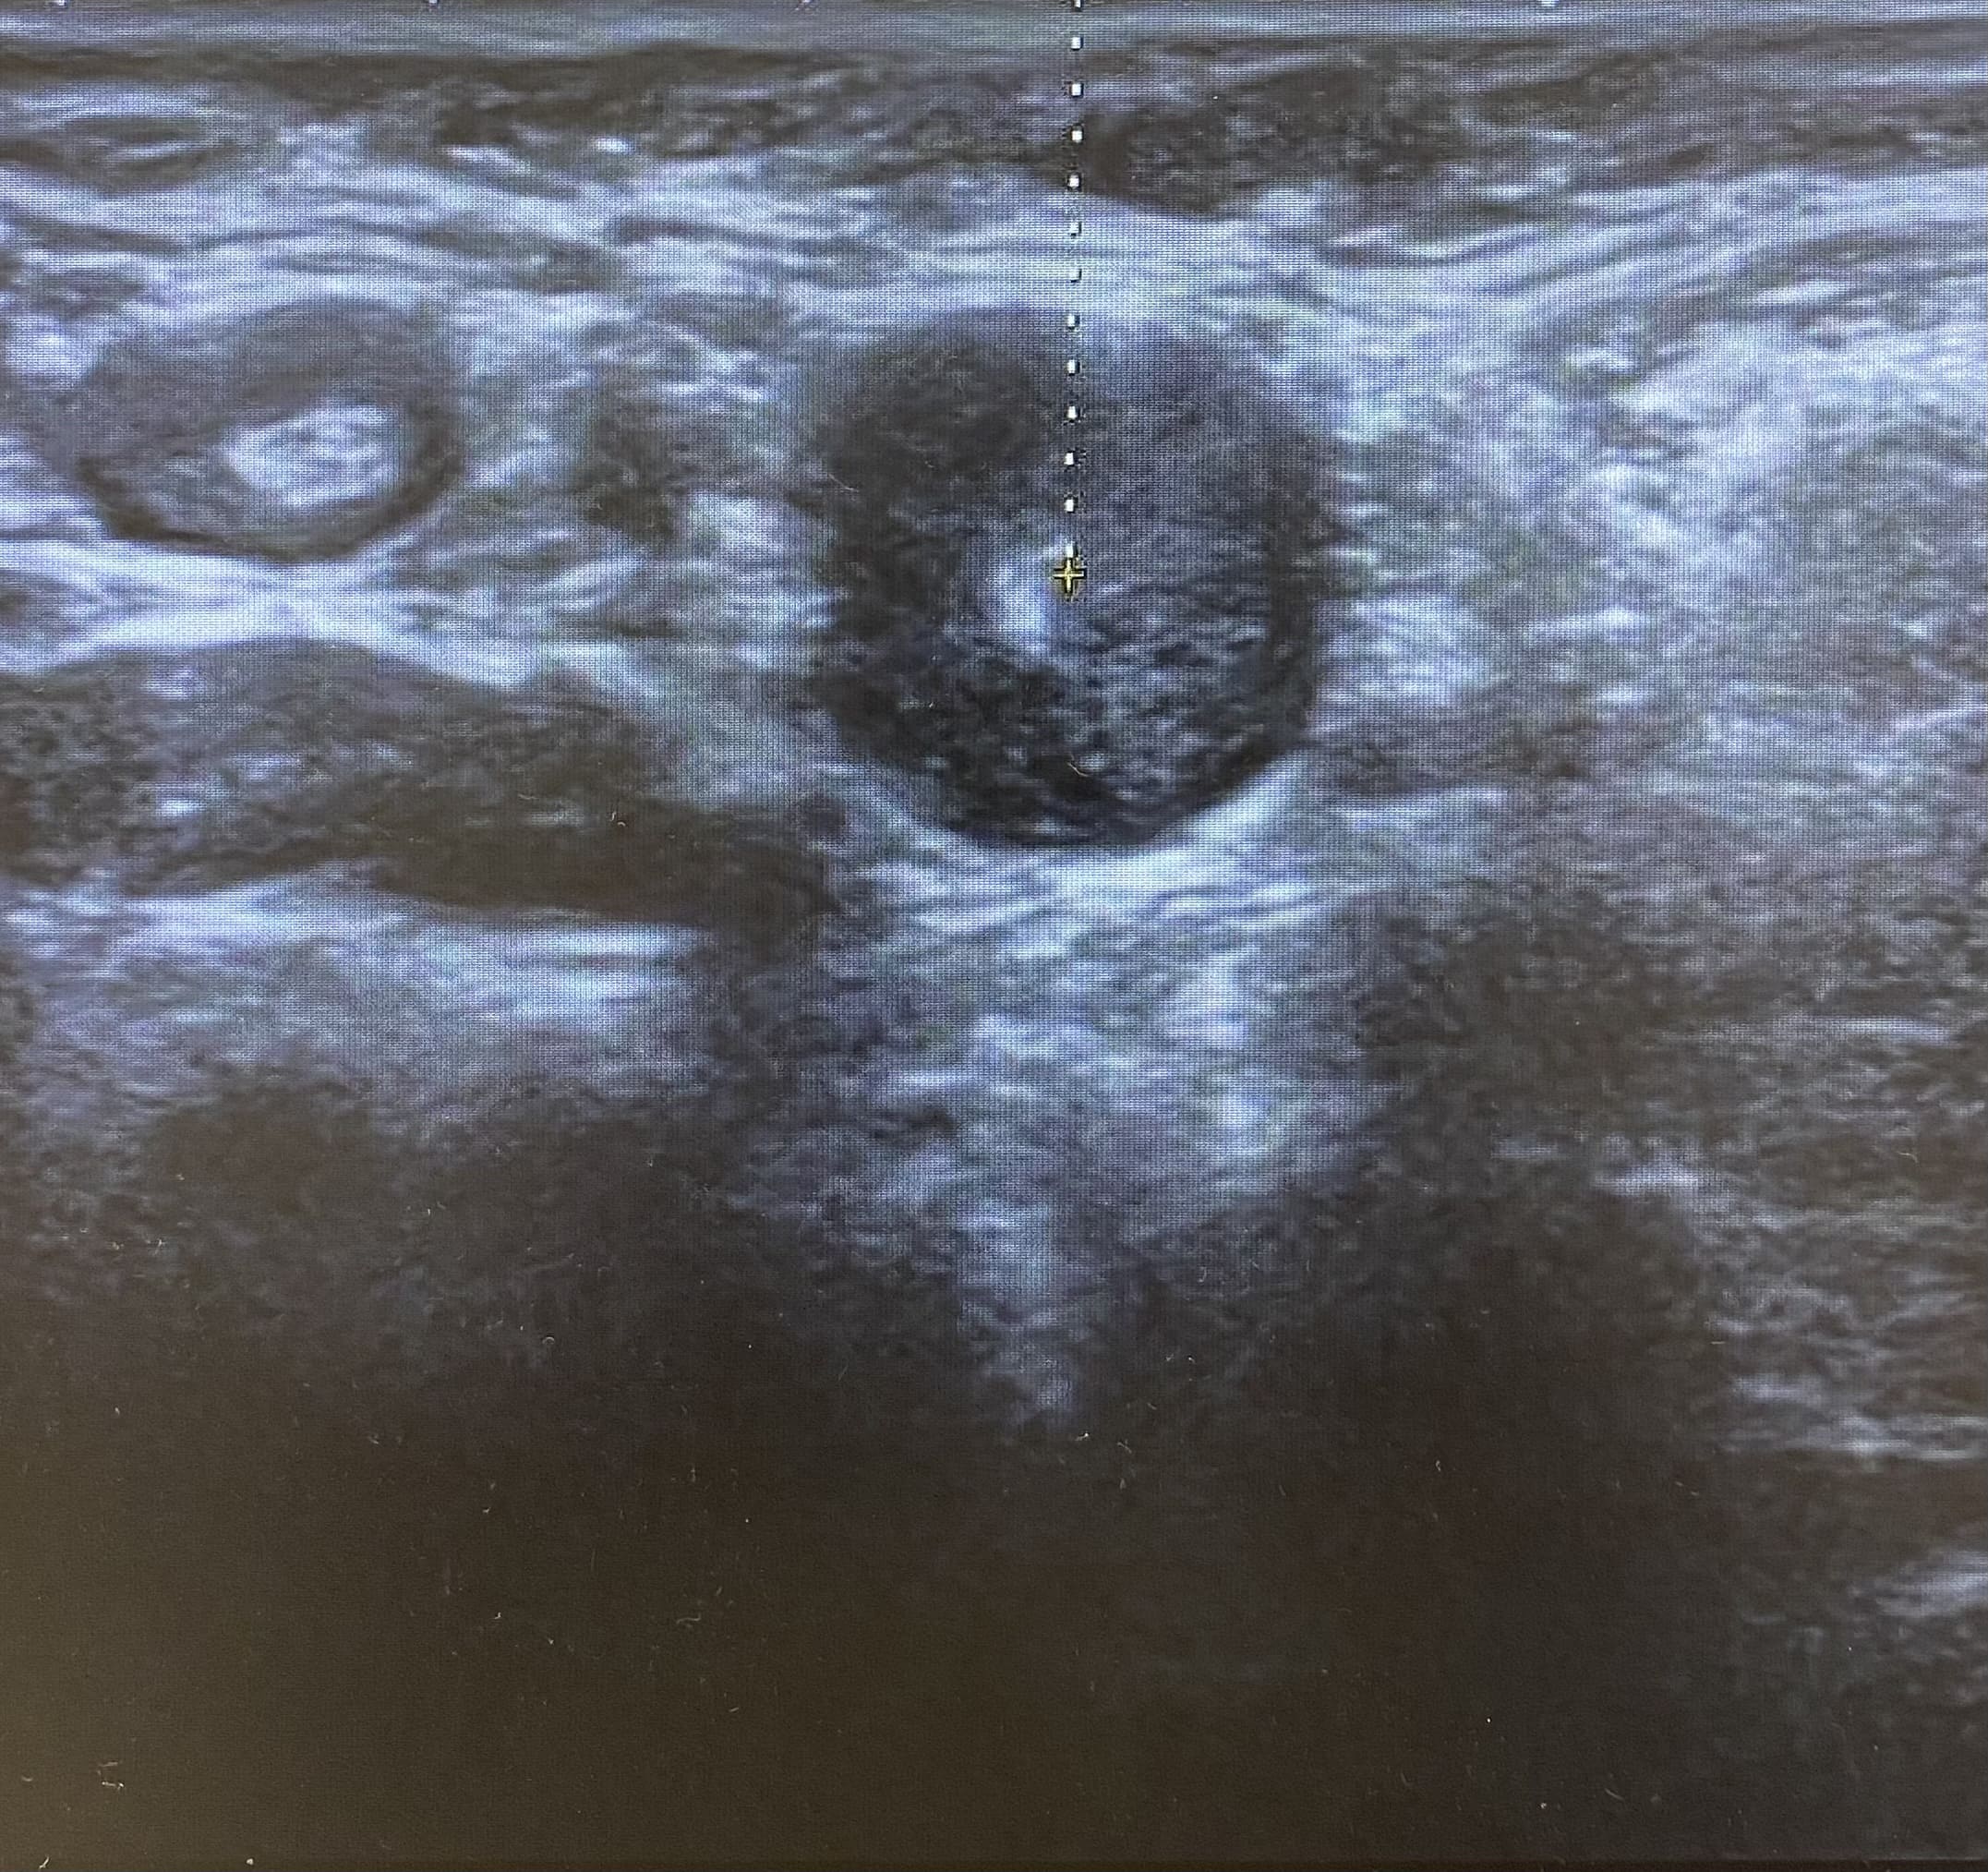

Ecografía: Valoración de adenopatías para acercamiento diagnóstico (típicas/atípicas).

Hallazgos ecográficos

Adenopatías patológicas, algunas redondeadas, con eje anteroposterior > 1 cm, parénquima homogéneo, cortical engrosada aunque con hilio respetado.

Ecografía mamas: quistes y nódulos hipoecogénicos bilaterales.

Ecografía axilar: múltiples adenopatías con eje corto > 2 cm y cortical engrosada.